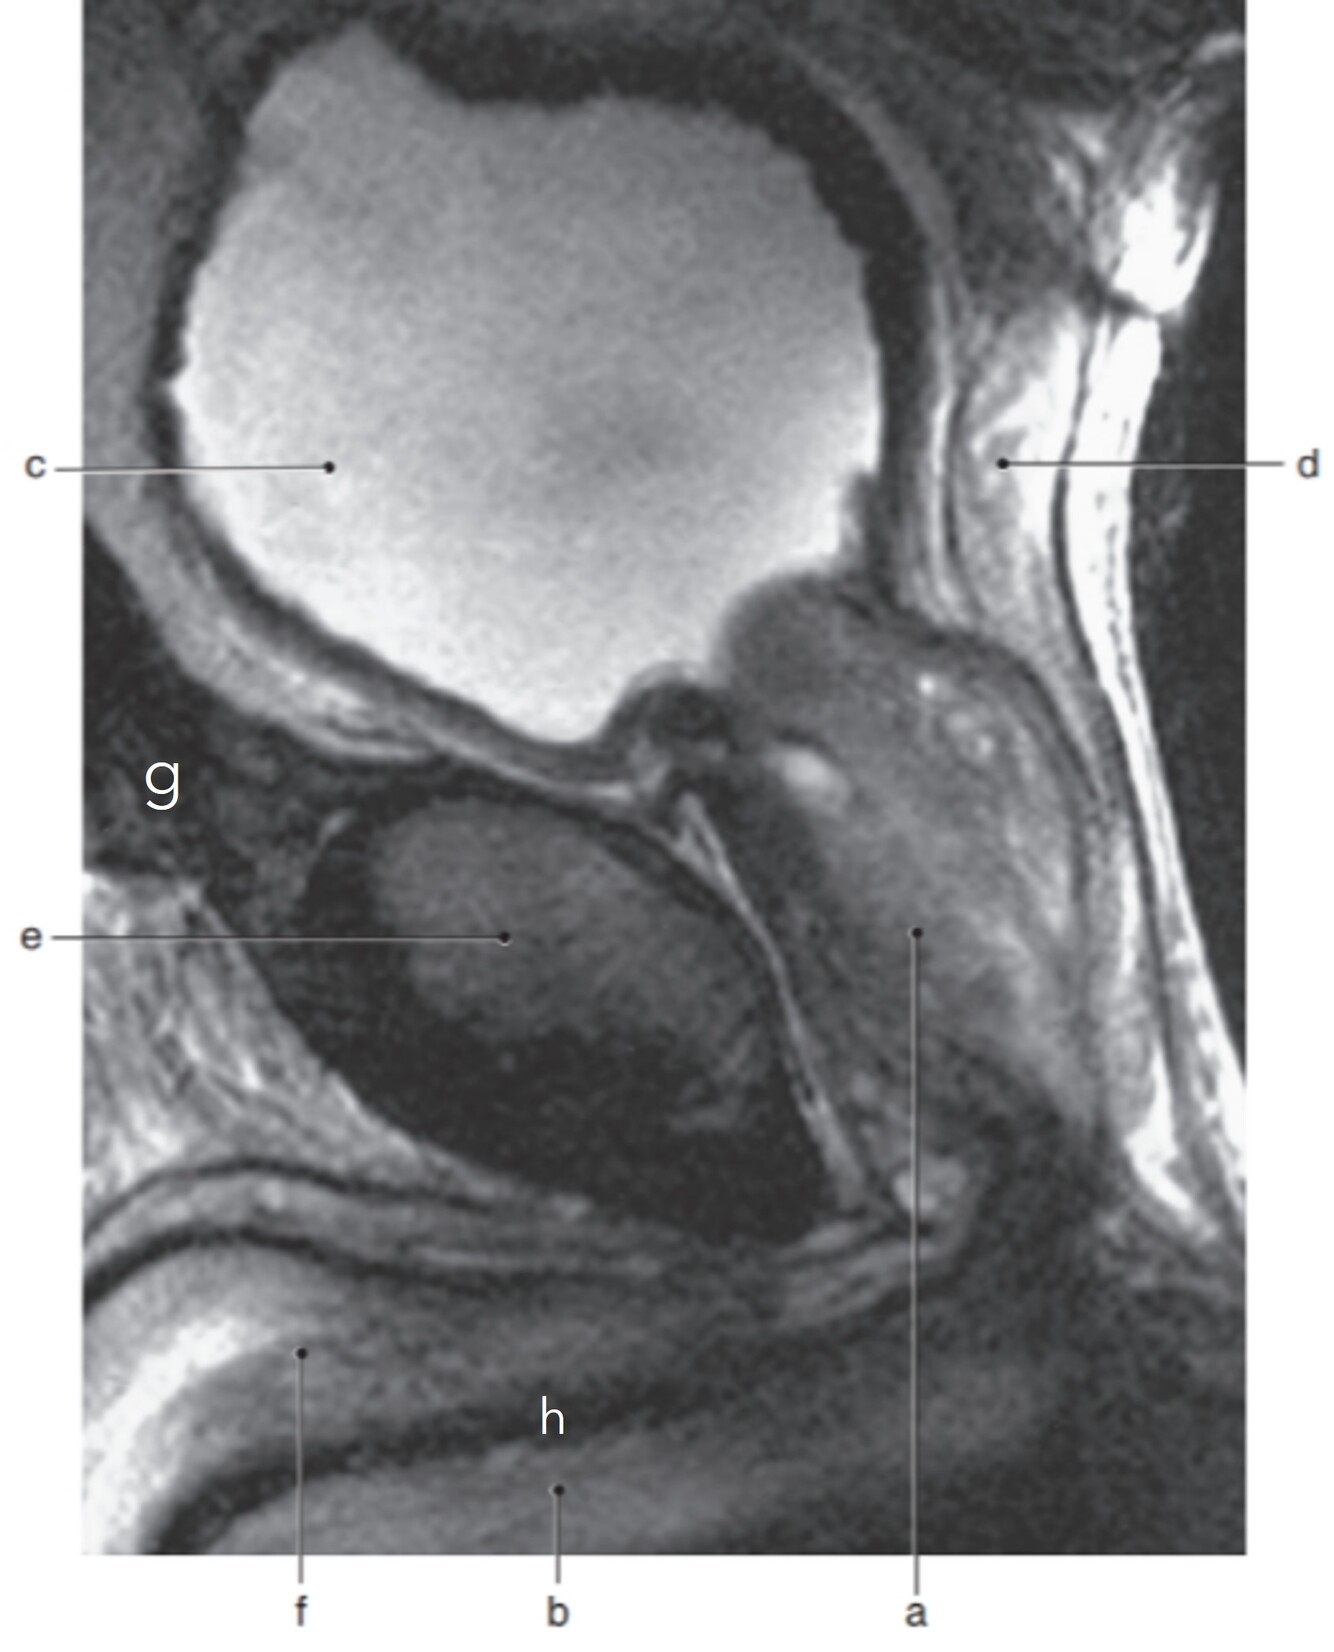

19

Q

Label a-d

A

a. Lt SI joint

b. Lt sacral foramina

c. Lt sacral nerve

d. Lt gluteus maximus